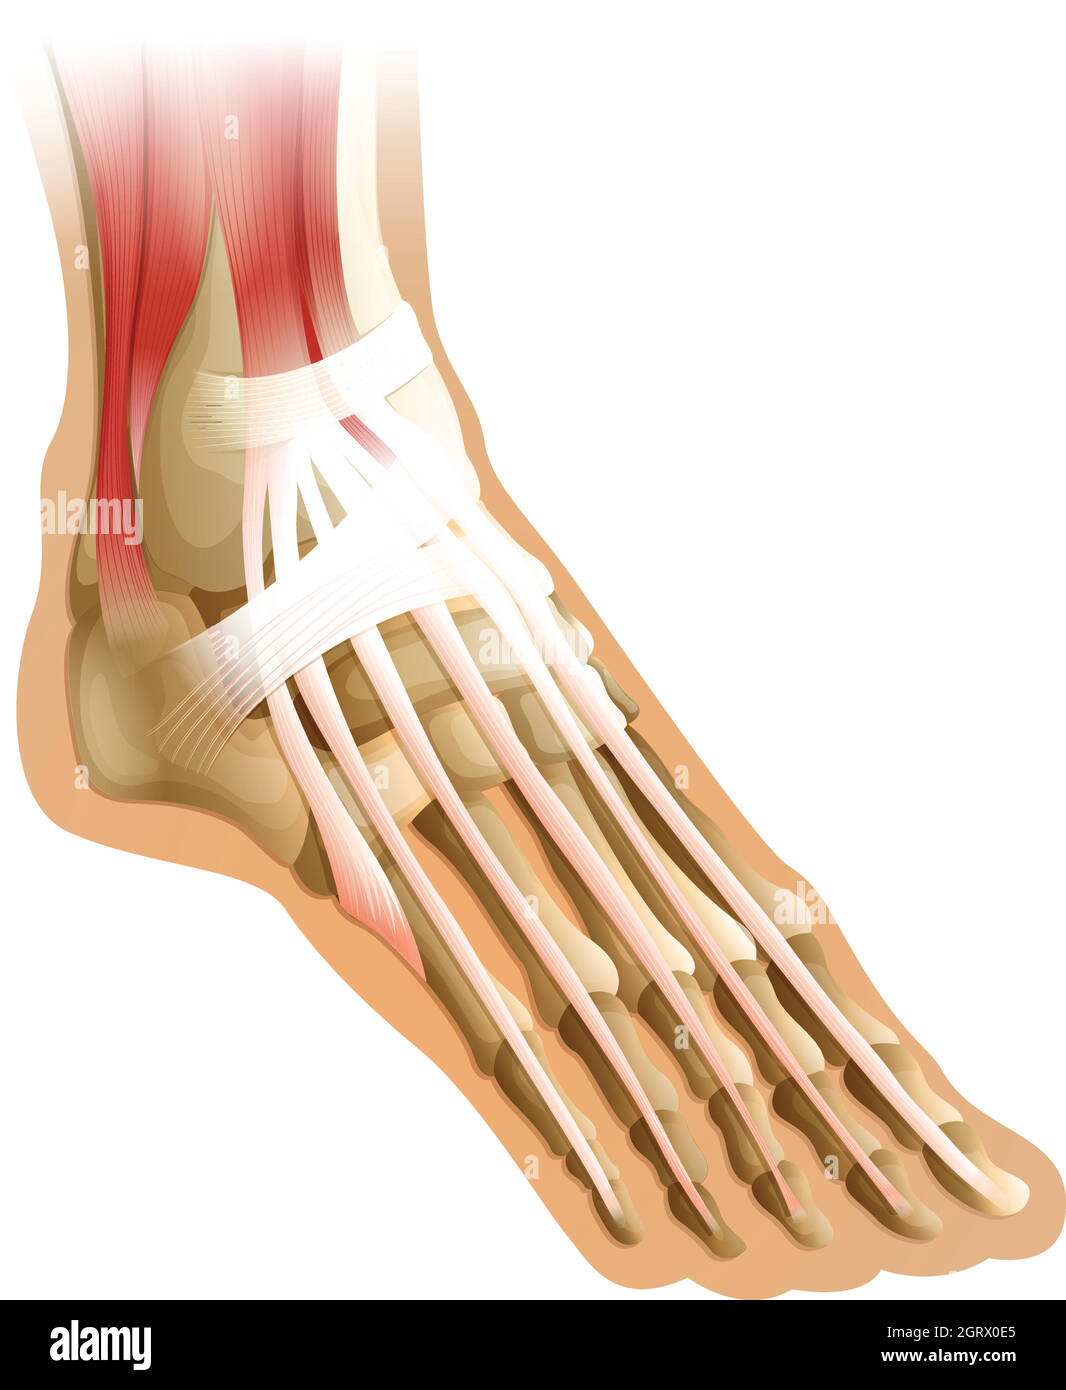

RF2HJXCXK–Anatomie du pied.OS et fascia Plantar.Illustration vectorielle réaliste. Vue de dessous et vue latérale